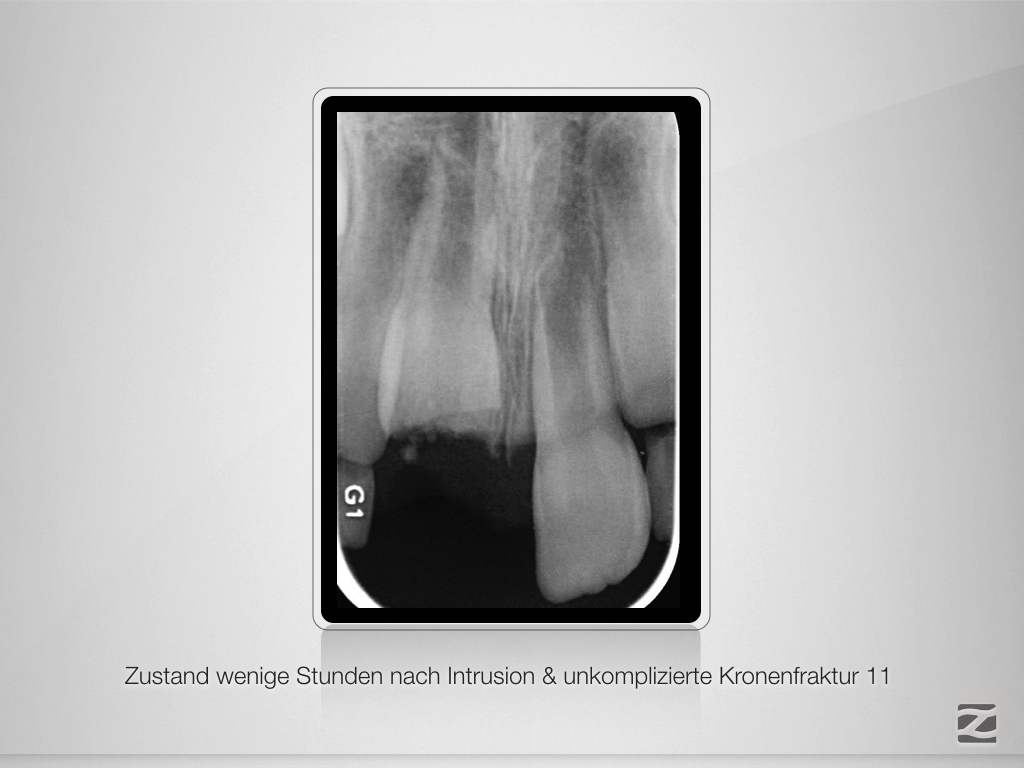

Bestmöglicher Kompromiss